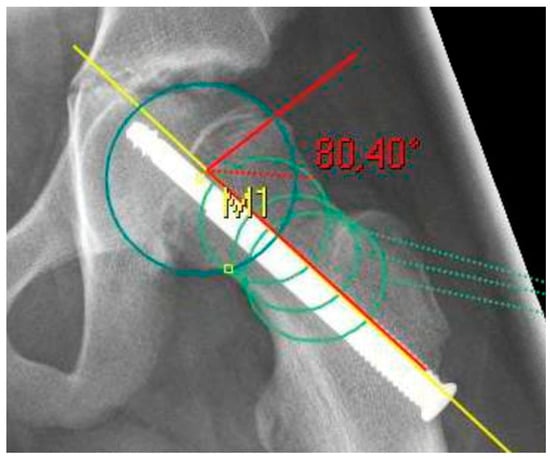

The radiological analysis directly after surgical fixation included the lateral center edge angle according to the sourcil method (LCEA) [22] and the acetabular angle (inclination) to evaluate the femoral coverage [23], especially regarding the presence of a hip dysplasia or coxa profunda, as well as the absolute slip angle according to Southwick [24,25]. The grading of the Southwick angle values is typically: mild (<30°), moderate (30–50°) and severe (>50°). Because the alpha angle is referenced to the femoral neck axis, this reference was the same for the posterior epiphyseal tilt to predict a FAI type cam over the time [26]. In contrast to the Southwick angle, which is determined as an angle between the slipped capital epiphysis and the femoral shaft axis, the posterior epiphyseal tilt was referenced also to the femoral neck axis like the alpha angle [27]. In addition, parameters for dysplasia resp. retroversion were evaluated, including the crossover sign (the anterior and posterior acetabular rims crossing on the pelvic a.p.) and the prominence of the ischial spine (PRISS; the ischial spine is projected in the lesser pelvic on the pelvic a.p.) [28]. In presence of a crossover sign and a positive PRISS a retroversion was assumed, whereas a dysplasia was defined with a LCEA <20 and an inclination >10°. All the described values were assessed again at the last time of the radiological follow-up, additionally the alpha angle [13]. In presence of a SCFE, the center of the femoral head is not always aligned to the axis of the femoral neck for measurement of the alpha angle and the posterior epiphyseal tilt. To avoid inaccuracy, the anatomical method according to Bouma et al. was used [29]. For this, the femoral neck axis was defined with three circles along the femoral neck, whichever fitted the bony neck best (Figure 1 and Figure 2).

Figure 1. X-ray after screw fixation of a left sided SCFE as an example for the measurement of the alpha angle. The femoral neck axis (yellow line) was determined with three circles (light green) according to Bouma [29].